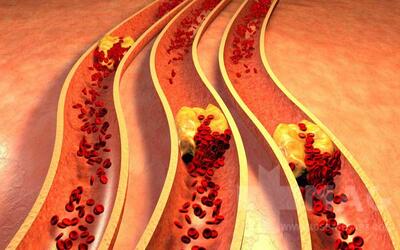

لخته شدن خون معمولا در کدام عضو بدن رخ می دهد؟ - خبرنامه

لخته شدن خون، یا ترومبوز، بخطرات جدی برای سلامتی دارد. عدم تحرک طولانی مدت، ضربه، اختلالات پزشکی و عوامل هورمونی از عوامل کلیدی هستند. افراد قد بلندتر به دلیل